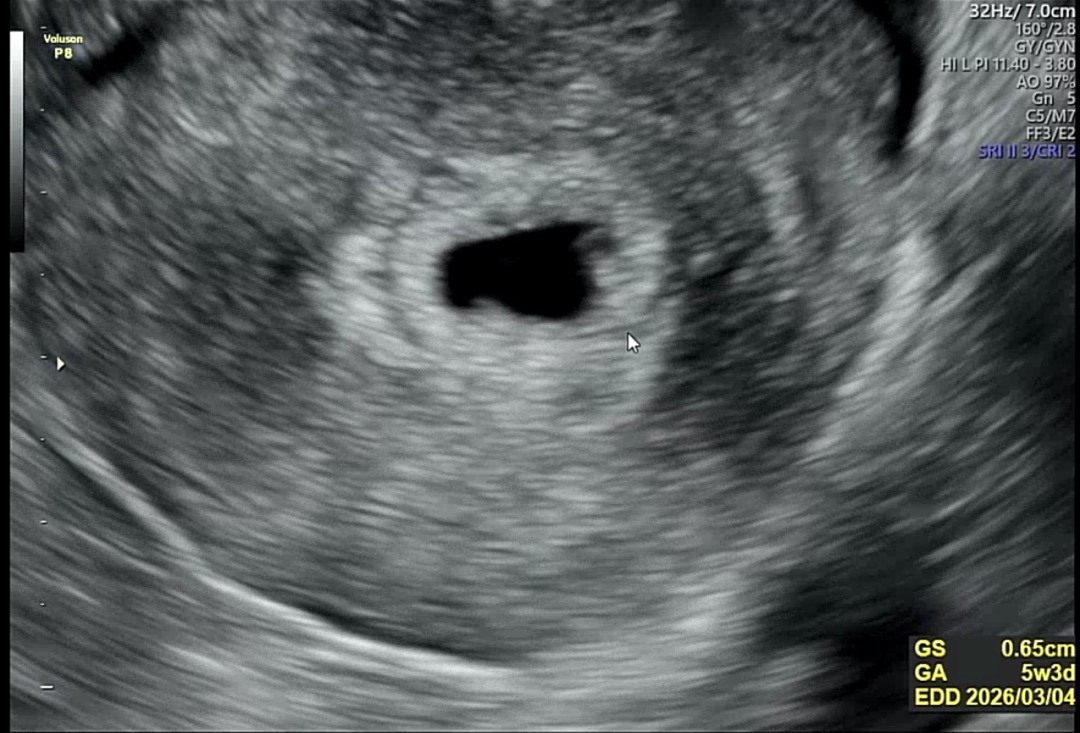

아기집 난황 보고 왔어요!

막생 5/27 쓰리라인 임테기 해보고 세줄다 찐했구요. 빌리에서 5주4일로 알고 갔는데 초음파에선 5주2-3일 이라고 했어요~ 무증상 이라고 글 남겼는데 난황봐서 마음이 약간 편해졌습니다 ㅎㅎ 오른쪽 위에 희미하게 보이는게 난황인데 선명하게 보이진 않더라구요. 우리모두 건강하게 아기 만날수 있길 기도합니다😊😊